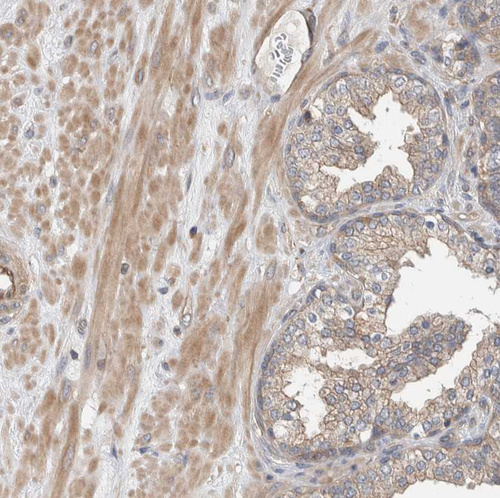

Immunohistochemical staining of human cerebral cortex, fallopian tube, liver and prostate using Anti-MPRIP antibody HPA022901 (A) shows similar protein distribution across tissues to independent antibody HPA022034 (B).